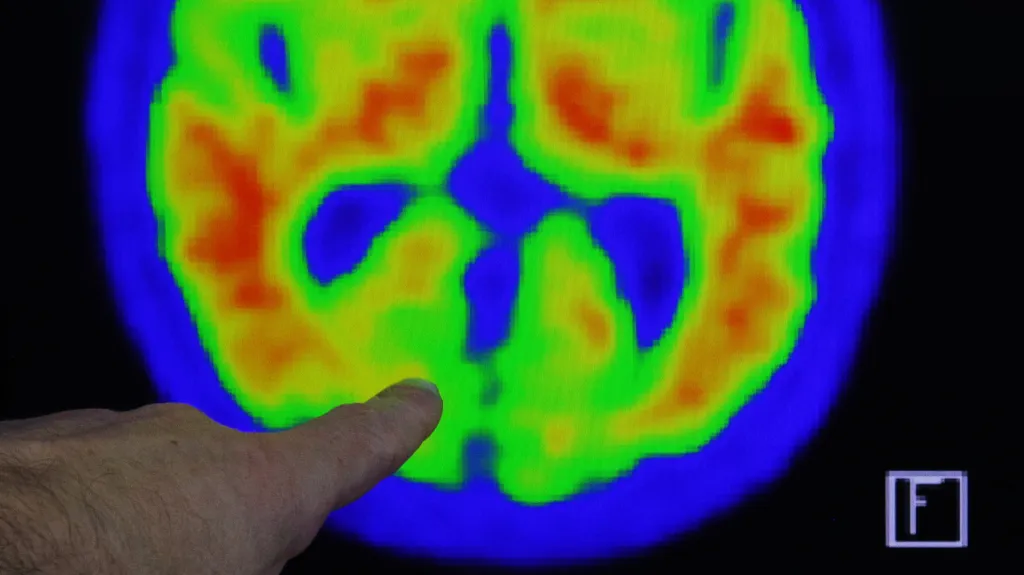

Alzheimerova choroba je oprávněně považovaná za jednu z nejobávanějších nemocí 21. století. V lidském mozku se při ní usazují bílkoviny odborně nazývané amyloidy. Dá se to velmi zjednodušeně připodobnit situaci, kdy se na vnitřní straně nějaké trubice nahromadí špína tak moc, až ji ucpe. Když se tak zmíněné bílkoviny kumulují, způsobují odumírání mozkových buněk a to vede právě ke vzniku Alzheimerovy choroby – tedy ke stále se zhoršujícím poruchám paměti, úsudku a postupně k nesoběstačnosti.